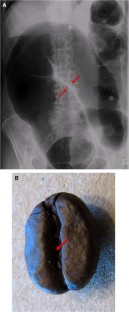

Coffee bean sign

Fig. 2

Chakraborty, A., Ayoob, A. & DiSantis, D. Coffee bean sign. Abdom Imaging 40, 2904–2905 (2015). https://doi.org/10.1007/s00261-015-0402-3

• Ischemia

• Perforation

• Closed Loop